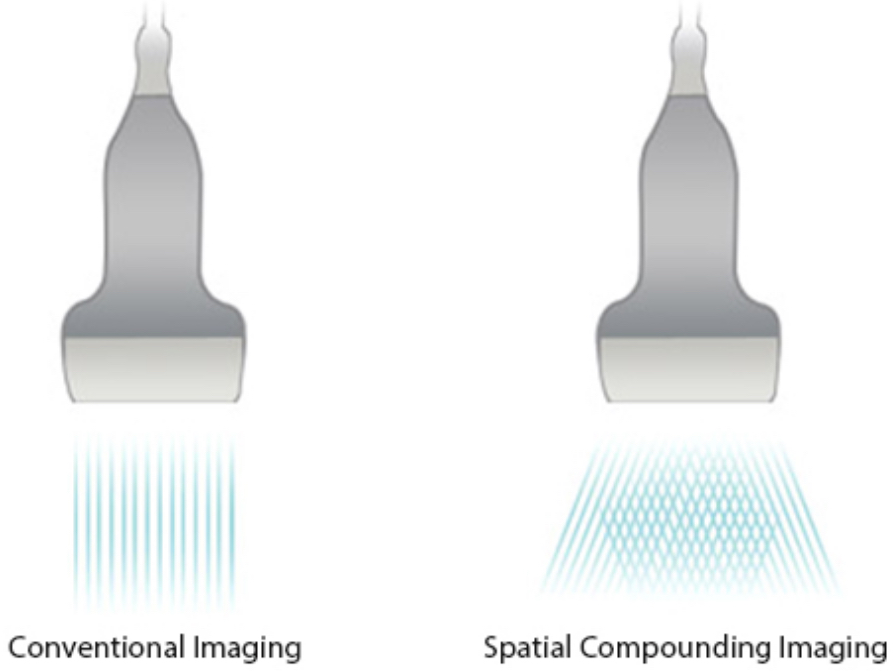

iBeam?

Sonucunda art?r?lm?? kontrast ??z├╝n├╝rl├╝?├╝ ve geli?mi? g?r├╝nt├╝leme imkan?na kavu?ulan tek bir g?r├╝nt├╝ olu?turmak i?in bir?ok tarama a??s?n?n kullan?lmas?na izin verir.